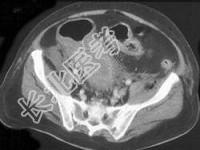

- 单项选择题男,18岁, 患者皮肤挫伤,用林可霉素预防感染, 次日大便次数增多、出现粘液便,结合图像应考虑为 ( )

B、假膜性肠炎